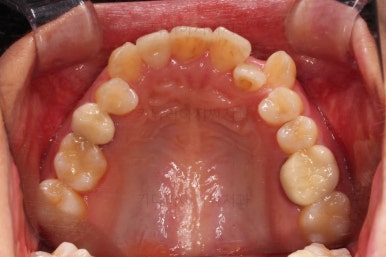

부산치과교정 키다리아저씨치과 초진 시 입안의 모습입니다.

확연히 좌우의 삐뚤어진 정도가 차이나죠.

덧니도 좌측(사진에서 보면 오른쪽) 위아래만 있는 상태고요.

좌측으로 삐뚤어져서 앞니도 좌측으로 쏠려 있는 상태였습니다.